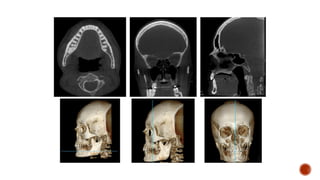

SECONDARY OR MULTIPLANAR RECONSTRUCTION

• The axial plane (X) is a horizontal plane that divides

the anatomical features within the FOV into superior

and inferior slices

• The coronal plane (Y) is a vertical plane that divides

the anatomical features within the FOV into anterior

and posterior slices

• The sagittal plane (Z) is also a vertical plane that

divides the anatomical features within the FOV into

right and left slices